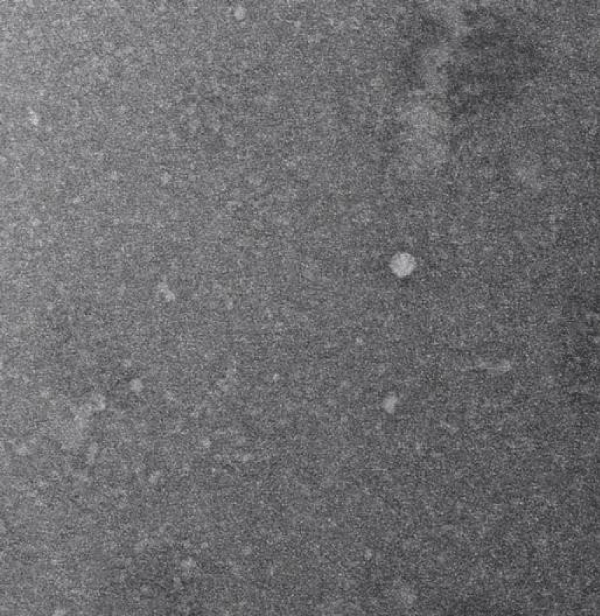

Electron Microscopy (EM) Analysis (Figure 1)

◦ Field of View: 50 nm.

◦ Magnification: 92,000x.

◦ Sample: Sheep brain cells.

Image Description: The EM image shows a granular background with scattered, brighter spots (5-20 nm in diameter), indicating a polydisperse mix of nanoscale fragments.

◦ The 5-20 nm particles are ideal for sublingual absorption, as particles <200 nm are optimal for mucosal uptake [4]. Particles >450 nm are less likely to be absorbed, supporting the need for filtration.

◦ The brighter spots suggest structured components (e.g., membrane fragments, protein aggregates, organelle remnants), indicating preserved bioactivity despite mechanical processing.

◦ Polydispersity highlights the need for refinement (e.g., filtration) to ensure uniformity, but the small size range confirms the protocol’s ability to produce absorbable fragments.